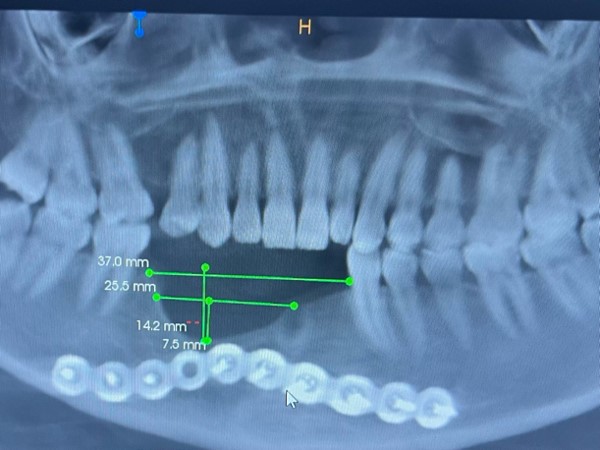

1.术前准备:通过螺旋CT(含三维重建)测量出患者骨缺损的长度与高度,确保手术精确性。